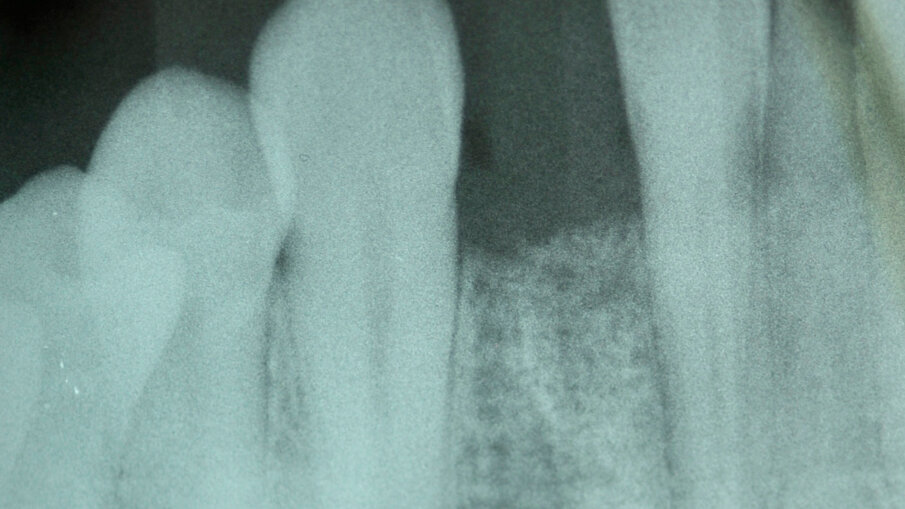

40letý pacient s chybějícím pravým postranním řezákem v dolní čelisti a štěpem transplantovaným do oblasti tohoto chybějícího zubu požádal o rekonstrukci za použití dentálního implantátu. U tohoto typu náhrady je problémem omezený dostupný prostor a blízkost sousedních zubů. Při klinickém vyšetření byl posouzen dostupný prostor (obr. 1) a na periapikálním RTG snímku pořízeném před ošetřením byla vyhodnocena oblast pro zavedení implantátu (obr. 2). Plán ošetření zahrnoval konvenční zavedení implantátu za použití implantátu OsseoSpeed EV (Dentsply Sirona) a bezprostředně po zavedení implantátu byla nasazena provizorní náhrada na abutmentu Temporary Abutment EV (Dentsply Sirona). Pro definitivní náhradu bylo naplánováno použít za účelem obnovy přirozeného vzhledu a funkce chybějícího zubu korunku na abutmentu Atlantis Crown Abutment (Dentsply Sirona).

Zavedení implantátu